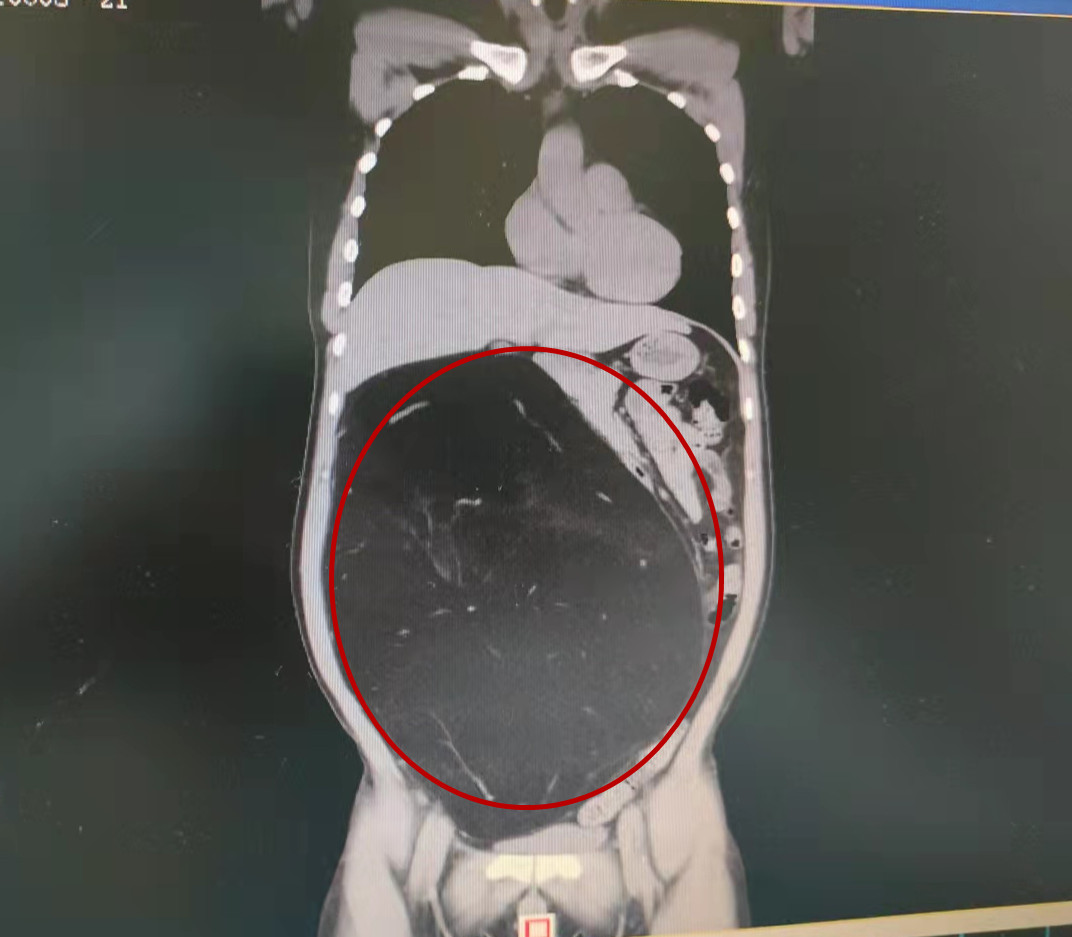

检查结果显示蒋先生肚子里的腹膜后巨大脂肪肉瘤

到捷克论坛 马王堆院区普外五科检查,发现肚子里长了个大瘤子,把肠子都压到一边去了,顾如山主任医师接诊了蒋先生,最终诊断为腹膜后巨大脂肪肉瘤,收治入院准备手术。

经缜密的术前准备,蒋先生接受了手术。手术由顾如山主任医师主刀、兰思根博士协助,在保护好其他脏器的前提下尽量完整切除脂肪肉瘤,手术非常成功,完整切除了大约36✘30✘15cm,重约6.73Kg的肿瘤,术后病理报告为去分化脂肪肉瘤。